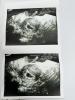

На 19дпп тоже кровь была. Лежала на сохранении в больнице. По хгч не подскажу, я не сдавала так как по узи уже видно было

На 18дпп уже узи делала